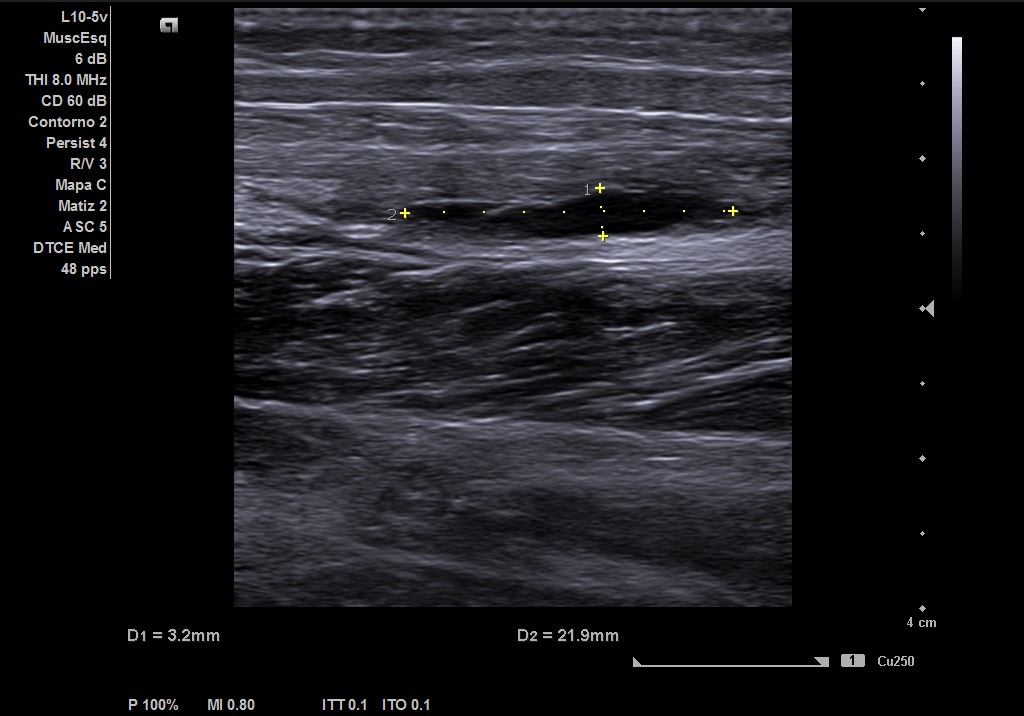

Descripción de los hallazgos ecográficos y las imágenes más relevantes para la resolución del caso

Ecografía musculoesqueletica: se objetiva signos de rotura de inserción gemeral interno-soleo de 21 x 32 mm y línea de líquido en zona superior intergastronemios de 1 mm de grosor. Doppler negativo.

Estamos ante una rotura fibrilar grado II según dicha clasificación.

Si correlacionamos la clínica, clasificación ecográfica y pronóstico. Nos encontramos con un grado II: Rotura Fibrilar. Pronóstico de 3 a 8 semanas.